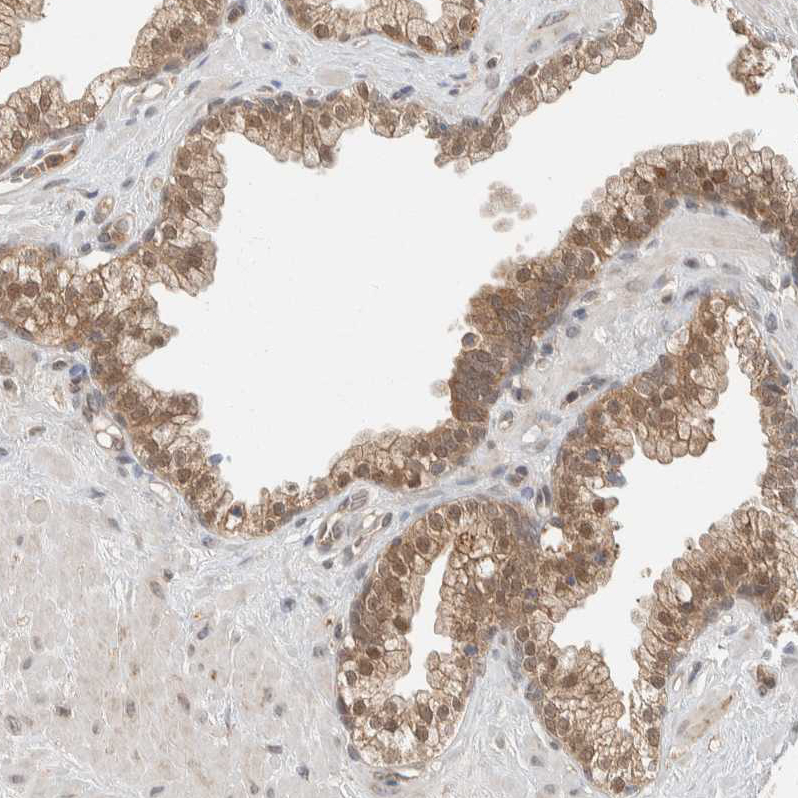

Immunohistochemical staining of human placenta shows moderate nuclear and cytoplasmic positivity in trophoblastic cells.